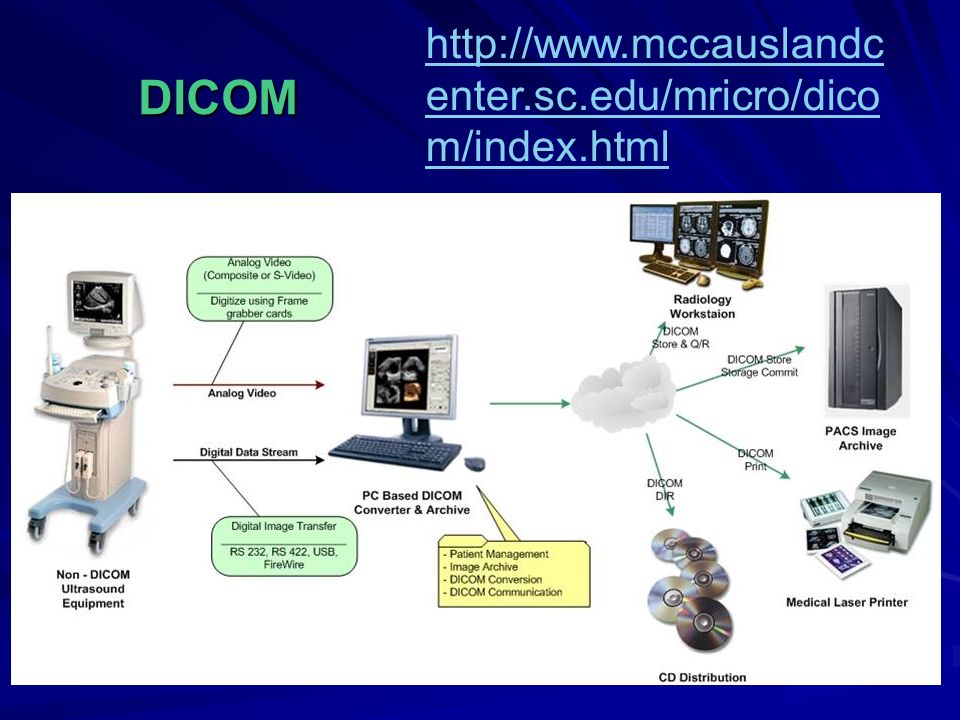

Лазерная камера сетевая для печати изображений на пленке стандарт dicom